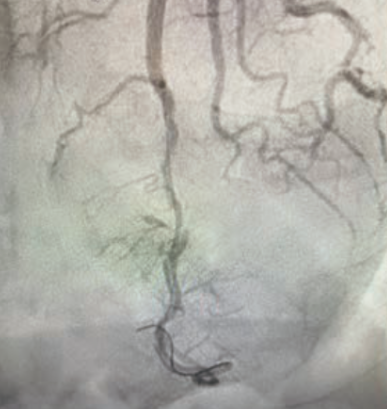

Figure 2 illustrates two cases of SCAD diagnosed in women with ST-elevation MI symptoms. In the first case, the patient was treated with medical therapy because the dissection was located too distal in the left anterior descending coronary artery to deploy a stent. The second patient was treated with a drug-eluting stent. Both patients had successful outcomes, and are also being managed with medications and regular cardiology follow-up care.